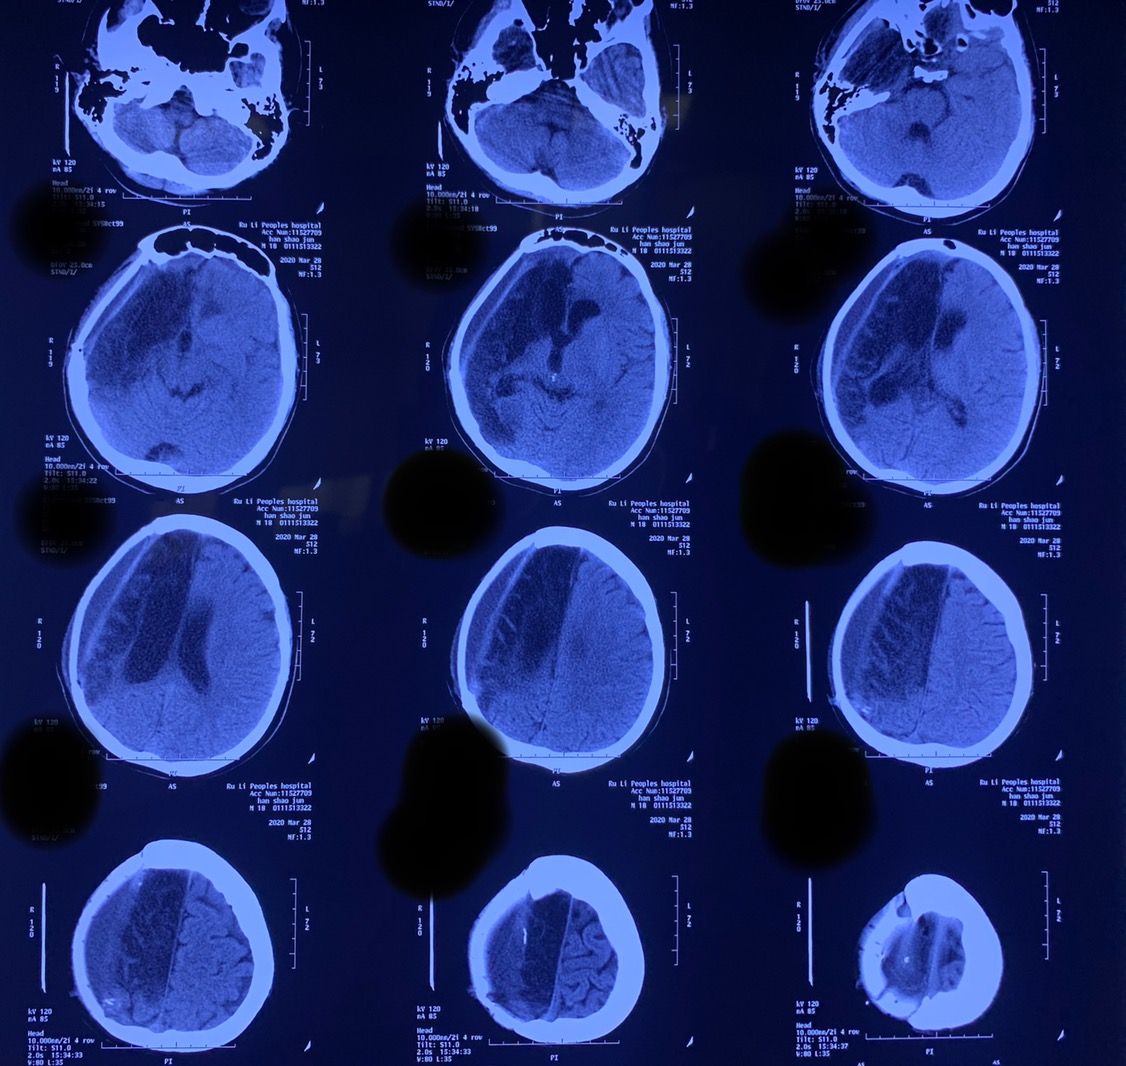

遂急诊行右侧额顶颞枕去骨瓣减压术,术后脑肿胀仍明显,骨窗张力极高。于10月17日请昆明医科大学第二附属医院神经外科蒲军主任会诊,蒲军主任详细了解病情并仔细分析影像学资料后决定再次手术扩大去骨瓣范围,并同时行内减压术。

再次手术后于10月18日复查CT

10月24日再次复查头颅CT:中线回移,脑室系统逐渐显示。此时骨窗压力亦明显下降。

术后复查CT